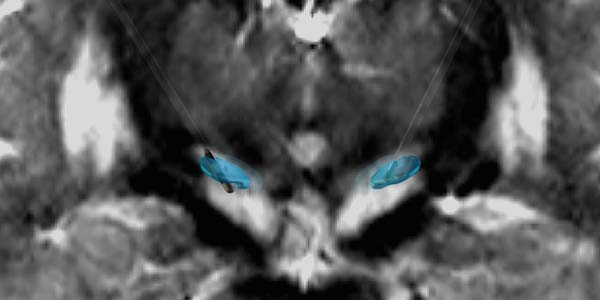

(宣武医院立体定向手术中的微电极记录、癫痫外科手术中的电生理监测以及神经电生理专业组人员)